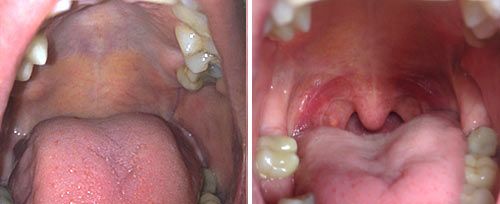

Before / after

NightLase Snoring Treatment

*Individual results vary. This treatment is not suitable for everyone. A consultation with a qualified practitioner is required prior to commencement.